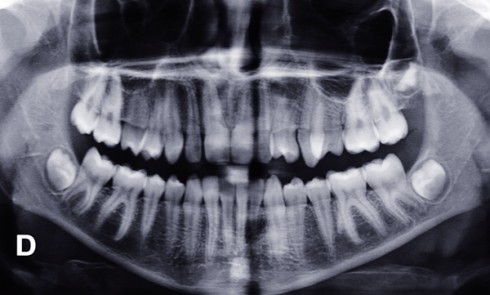

Article réservé à nos abonnés Parodontites terminales et échecs de réhabilitations implantaires maxillaires

Les indications L’état de délabrement des dents maxillaires ou du parodonte conduit parfois à poser l’indication d’une édentation totale. Une...